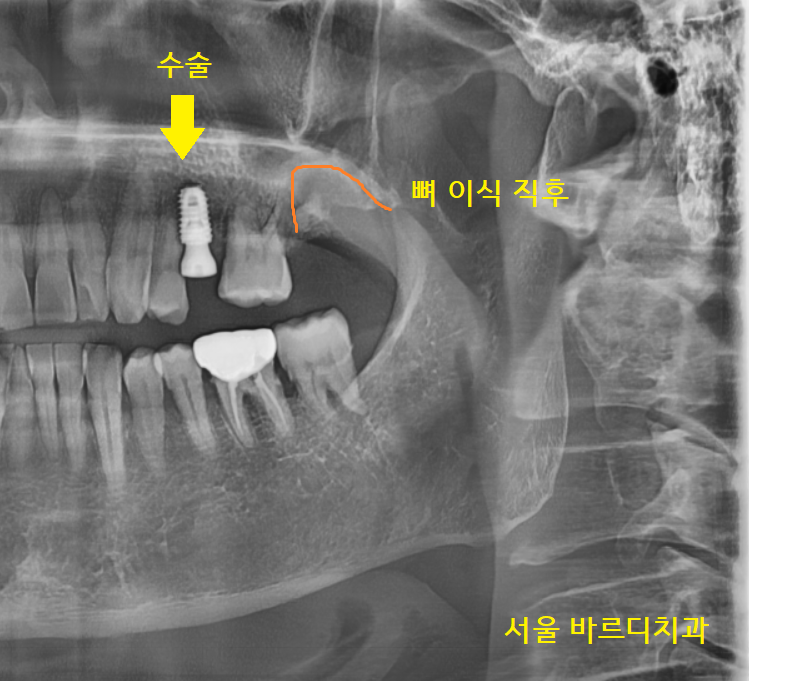

22.12.28

덕풍동 치과에서

이미 발치가 된 치아는 임플란트 수술을 진행하고

타 병원에서 임플란트 불가 판정을 받은

맨 끝 치아

잇몸 뼈가 부족한 상황이라

발치 후 뼈이식을 먼저 진행했습니다.

이전 글 확인하시고 오시면 잘 아시겠지만

뼈이식이 제대로 됐을 경우

돔 형태로 예쁘게 만들어져야 하는데요.

수술 직후 찍은 x-ray에서

돔 형태의 경계를 확인했습니다!